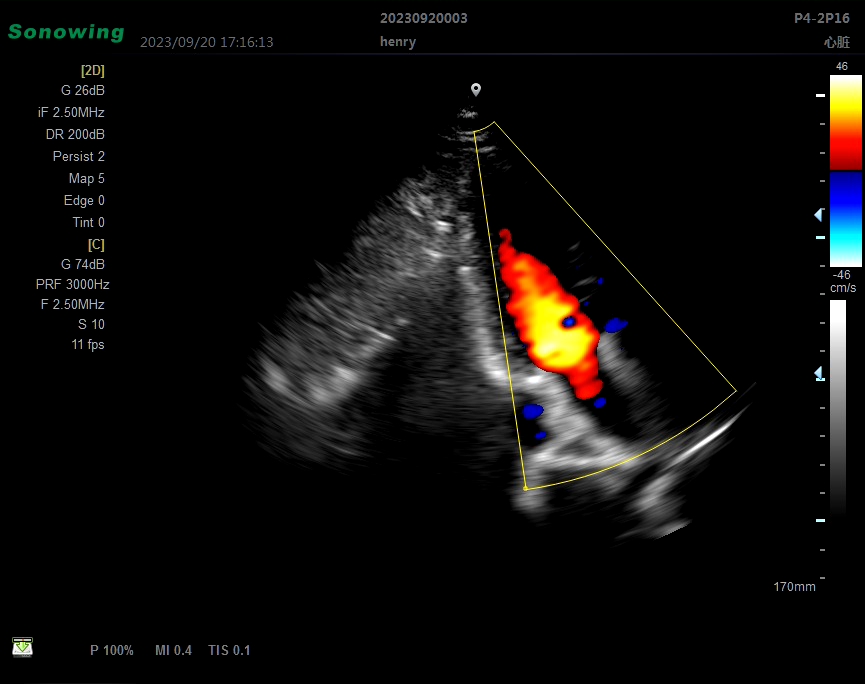

DMU07 Medical Instruments Gynecology Obstetric Portable Full Digital usg Ultrasound

Main Feature:Two probe connectors,15” LCD Flat Screen,Build-in Large Capacity BatteryMain Parameter:Scanning mode: Convex, Cavity, linear, Micro-convex, Phased array,4DModes: B, B/B,B/M,CFM,CFM/B,PDI,PDI/B,PW.CW B/D/PW real-time T...